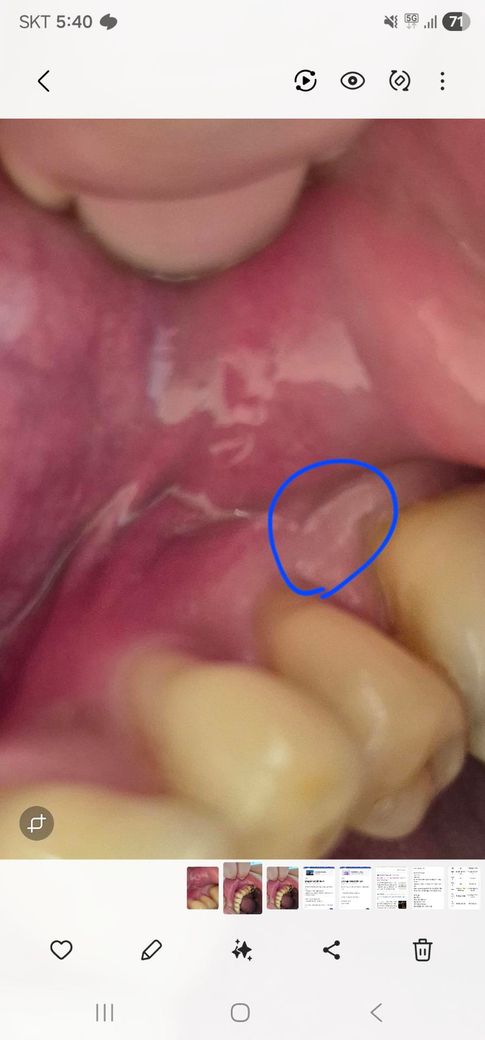

사진에 동그란 부분에서 아래 선처럼 내려오는것 같습니다.짠맛 때문에 치과를 몇번 갔으나 원인을 못찾았는데 오늘 사진 찍어보니까 이렇게 흐릅니다. 이 흐르는 액체 때문에 짠맛이 나는것 같은데 이렇게 투명 액체가 겉에서 나올때 치료는 어떻게 하나요.